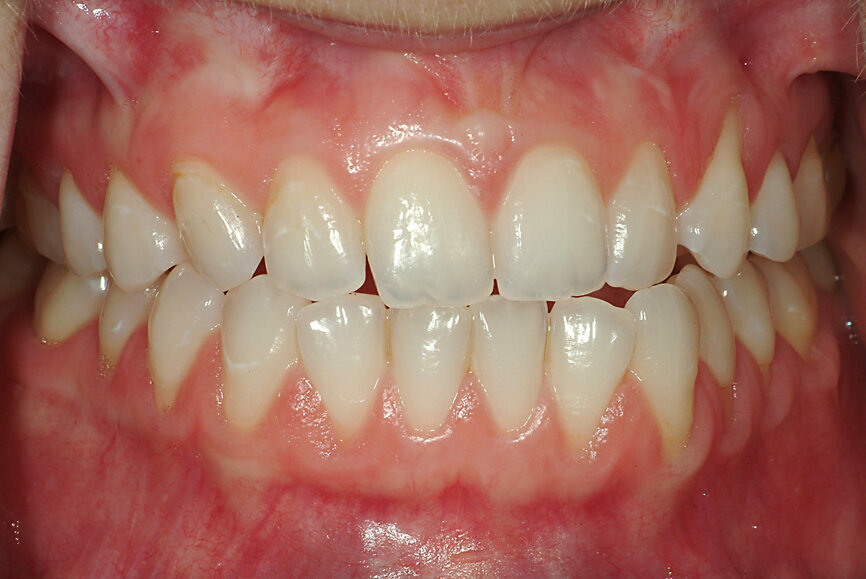

Fig. 13: Intercuspation requiring opening of the vertical dimension for restorative space.

Fig. 14: Significant wear requiring occlusal coverage and altering

of occlusion.

Fig. 17: Treatment modalities to recreate intercuspation in the new mandibular position.